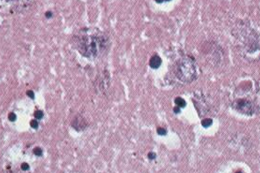

Тельца Бабеша-Негри